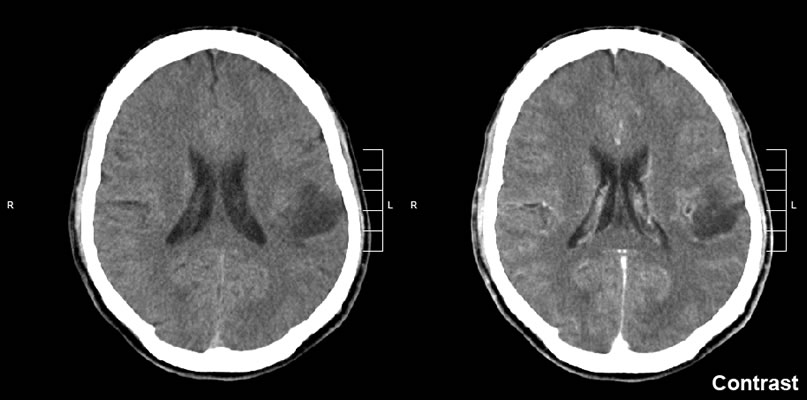

به گزارش نوروسافاری به نقل از ایرنا، این مطالعه نشان می دهد که هرچه افراد زمان بیشتری را برای تفکر در مورد مسایل مختلف، از جمله تحلیل یک فیلم یا تصمیم در مورد نوع غذای شام، صرف کنند، بافت غیر طبیعی این تومور خاص بزرگتر می شود. این تومور خاص وابسته به فکر، گلیوم پیشرفته (گلیوم درجه بالا) نام دارد.

glioma-brain-scan